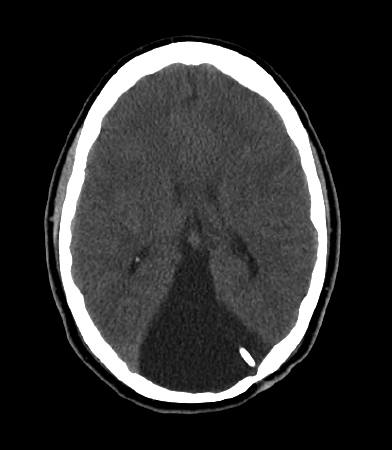

Before surgery, patients undergo a thorough evaluation to confirm the diagnosis of hydrocephalus and determine the best treatment approach. This typically includes neuroimaging studies such as MRI or CT scans to visualize cerebrospinal fluid (CSF) flow and measure ventricular size. Doctors also review the patient’s symptoms, overall health, and medical history to ensure shunt placement is the most effective option.